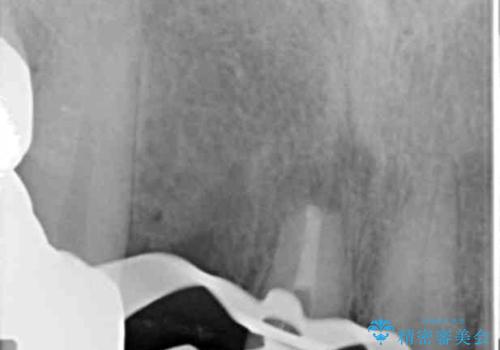

視診・X線写真検査より根尖性歯周炎が認められ再治療が必要な状態です。

再根管治療を行うべくクラウン除去を行ったところ、右上側切歯に保存不可能な垂直性の破折が認められたため抜去が必要になりました。